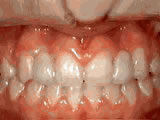

Crowding of the teeth

crowning of teeth

After

Patient started treatment at age 11 and wore braces for 26 months. He loves his new smile.